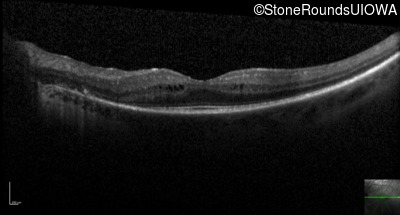

Optical Coherence Tomography - Right - 20/40 -1

Exemplar / OCT Stack

OCT Stack